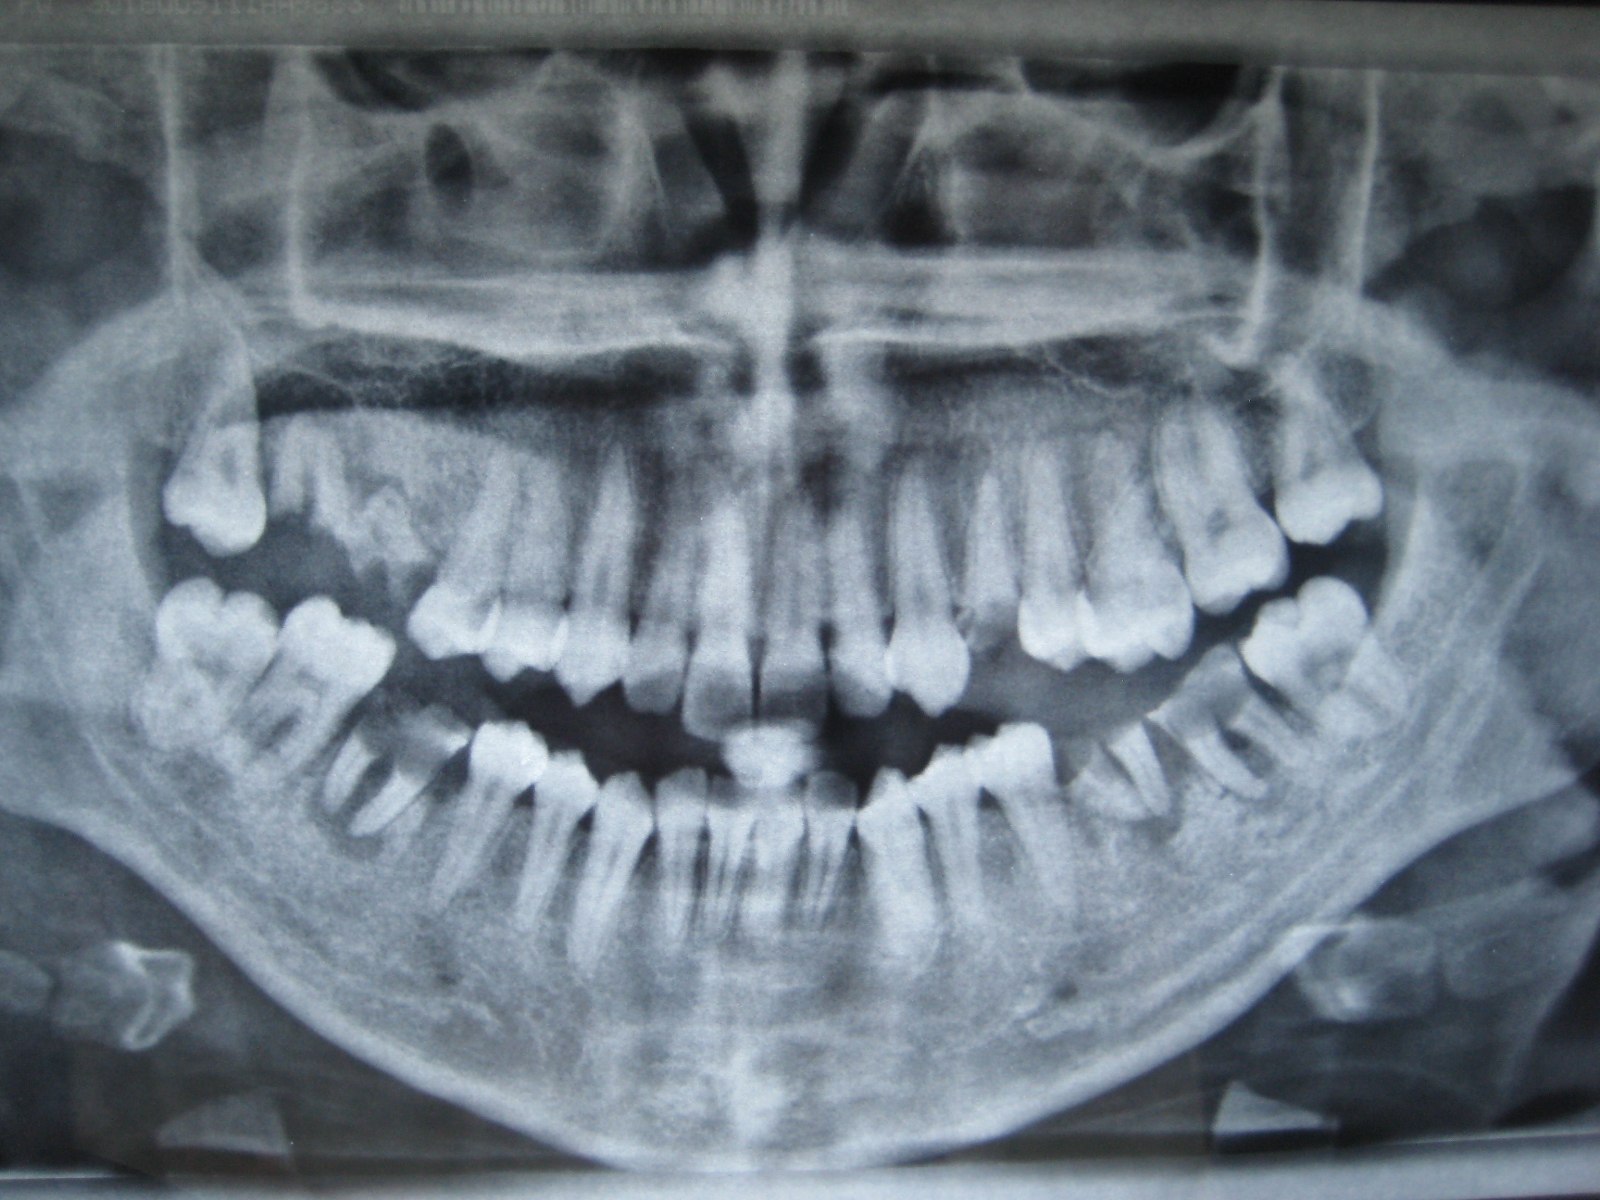

Vorrei avere qualche parere sulla mia (disastrosa) attuale situazione

30-05-2013